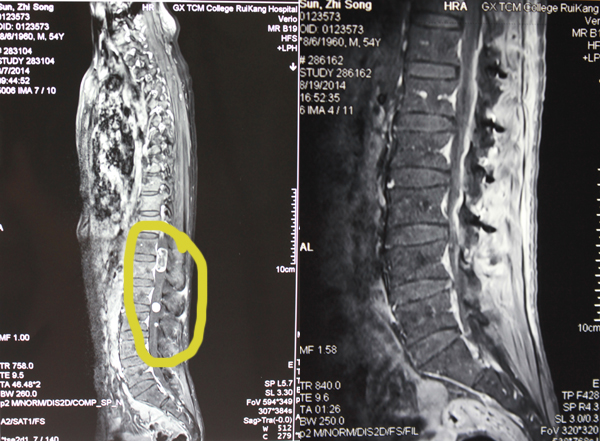

胡医生在分析治疗方案时说:“老孙椎管内的三个肿瘤分别为2.5*1.5cm,1*1cm,0.6*0.6cm,大小,从磁共振片上看,排在一起就像长了一串小果子。这样的多发性肿瘤在临床上是比较罕见的。”

由于病灶数量多,占四个阶段(T12—L3),所以手术有一定的困难。因为较大的肿瘤与脊髓圆锥关系密切,肿瘤有可能无法完整地被切除,一旦术中损伤了脊髓圆锥,术后很可能出现大小便失禁、性功能障碍、截瘫等严重并发症,从而影响今后的生活质量。

在充分的准备后,胡栓贵医生在全麻下行手术,首先切开软组织,然后完整取下胸12到腰3阶段的棘突及椎板,接着在显微镜下小心分离椎管内的肿瘤,由于肿瘤与脊髓圆锥粘连不严重,顺利全切肿瘤,之后用钛板复位棘突及椎板。

手术前后对比照片